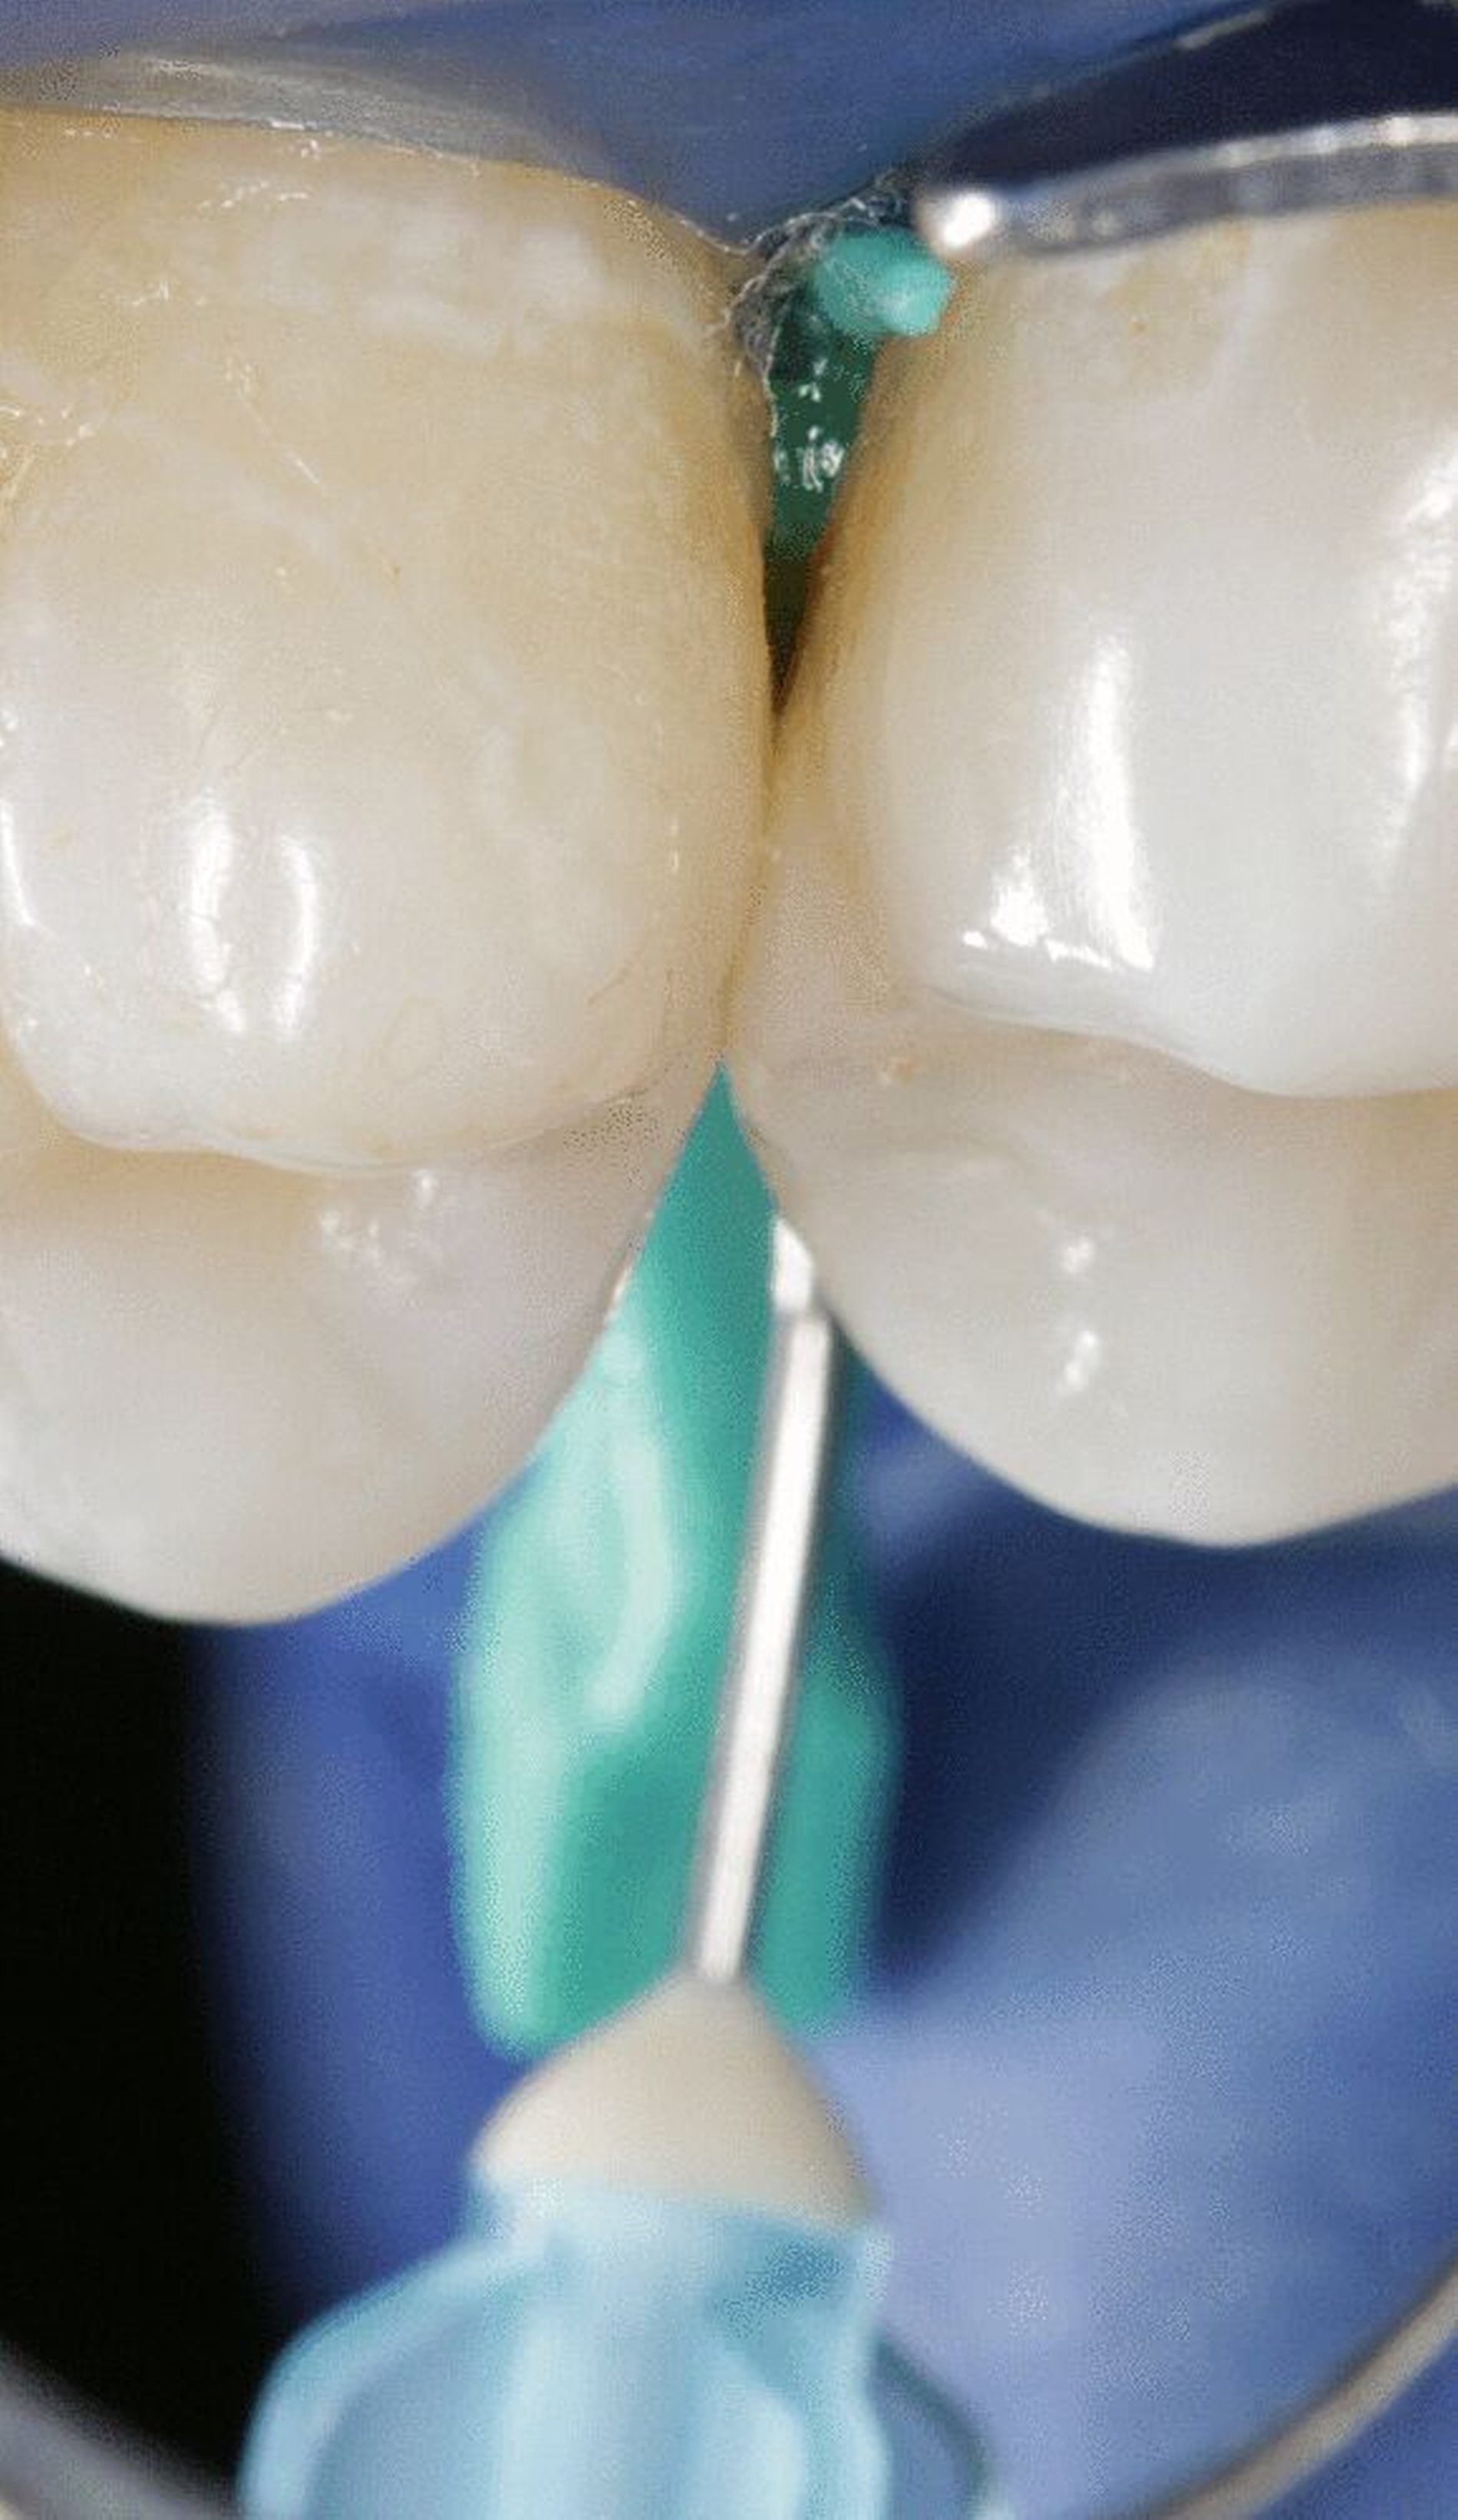

Bisher gibt es ein Produkt zur Kariesinfiltration (Icon, DMG, Hamburg), das alle relevanten Agenzien (HCl-Gel 15 Prozent, Ethanol 99 Prozent und Infiltrant) und ein Keilchen zur Separation enthält. Allerdings sollte vor der Behandlung nach dem Legen von Kofferdam und der Verwendung des Keilchens unbedingt mittels Sondierung [Paris et al., 2019] nochmals darauf geachtet werden, dass nicht versehentlich eine kavitierte Läsion behandelt wird, da selbst Mikrokavitationen nur unzureichend mit dem Infiltranten aufgefüllt werden können und somit die Läsion nur unzureichend arretiert bleibt.

Insofern an benachbarten approximalen Flächen nur eine zu infiltrierende Karies vorliegt, empfiehlt sich die Benutzung des in der Packung befindlichen Folienbügelhalters (Icon, DMG, Hamburg), der mithilfe abgeflachter Keilchen approximal eingebracht wird (Abbildung 1a). Es ist also keine vorherige aufwendige Separation der Zähne notwendig; die Behandlung erfolgt in einer Sitzung. Wenn an benachbarten Approximalflächen zu infiltrierende Läsionen diagnostiziert werden, können diese ohne Zuhilfenahme der Folienbügelhalter behandelt werden (Abbildungen 1b und 1c). Dies spart nicht nur Zeit, sondern auch Material, da neben der gleichzeitigen Behandlung von zwei Läsionen auch der Totraum der hierbei verwendeten Kanülen wesentlich kleiner ist als derjenige der Folienbügelhalter. Somit reduziert sich der Materialpreis pro behandelter Läsion deutlich. Eine Auflösung des approximalen Kontaktpunktes oder eine „Verklebung“ der approximalen Flächen ist bei gewissenhafter Entfernung des überschüssigen Kunststoffs vor der Lichthärtung nicht zu befürchten. Zur ausführlichen Beschreibung der Grundlagen, der Entwicklung und der Anwendung der Technik in Einzelschritten verweisen wir auf unsere Übersichtsarbeiten [Meyer-Lückel und Paris, 2011; Meyer-Lückel und Paris, 2012].